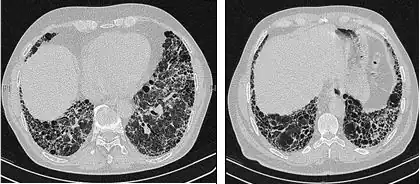

Chest X-rays are useful in the follow up routine of IPF patients. Plain chest X-rays are unfortunately not diagnostic but may reveal decreased lung volumes, typically with prominent reticular interstitial markings near the lung bases.[3]

The radiological evaluation through HRCT is an essential point in the diagnostic pathway in IPF. HRCT is performed using a conventional computed axial tomographic scanner without injection of contrast agents. Evaluation slices are very thin, 1–2 mm.

Typical HRCT of the chest of IPF demonstrates fibrotic changes in both lungs, with a predilection for the bases and the periphery. According to the joint ATS/ERS/JRS/ALAT 2011 guidelines, HRCT is an essential component of the diagnostic pathway in IPF which can identify UIP by the presence of:[3]

- Reticular opacities, often associated with traction bronchiectasis

- Honeycombing manifested as cluster cystic airspaces, typically of comparable diameters (3–10 mm) but occasionally large. Usually sub-pleural and characterized by well-defined walls and disposed in at least two lines. Generally one line of cysts is not sufficient to define honeycombing

- Ground-glass opacities are common but less extensive than the reticulation

- Distribution characteristically basal and peripheral though often patchy.